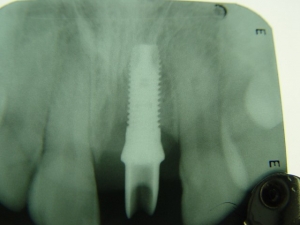

צילום השתל עם המבנה לקראת השיקום

סיום הטיפול